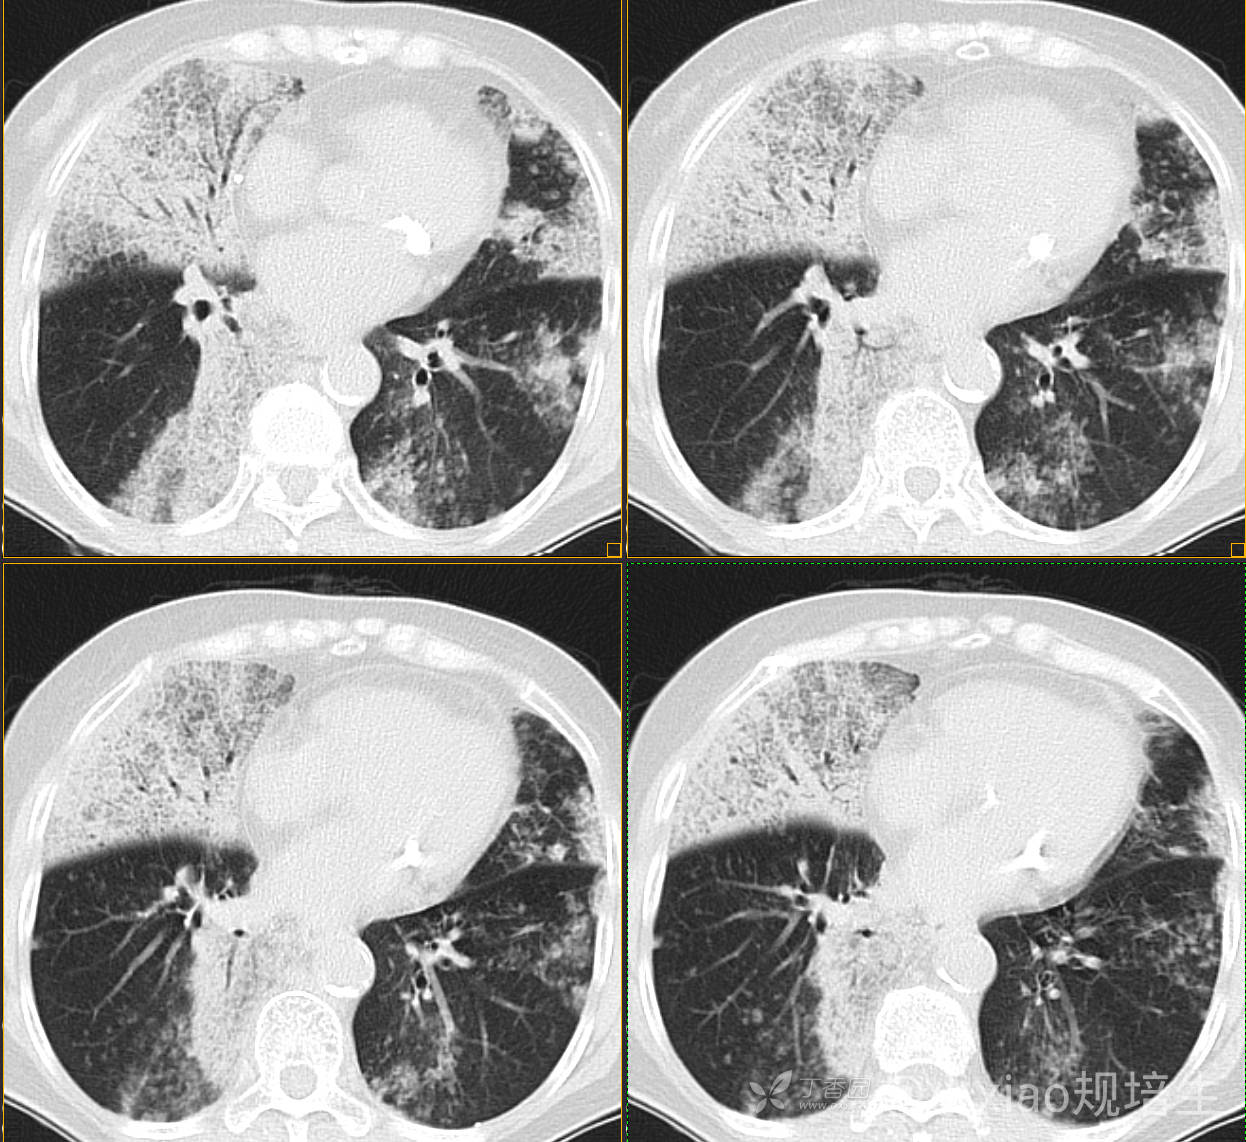

患者,女,89岁

咳嗽,咳痰一月余